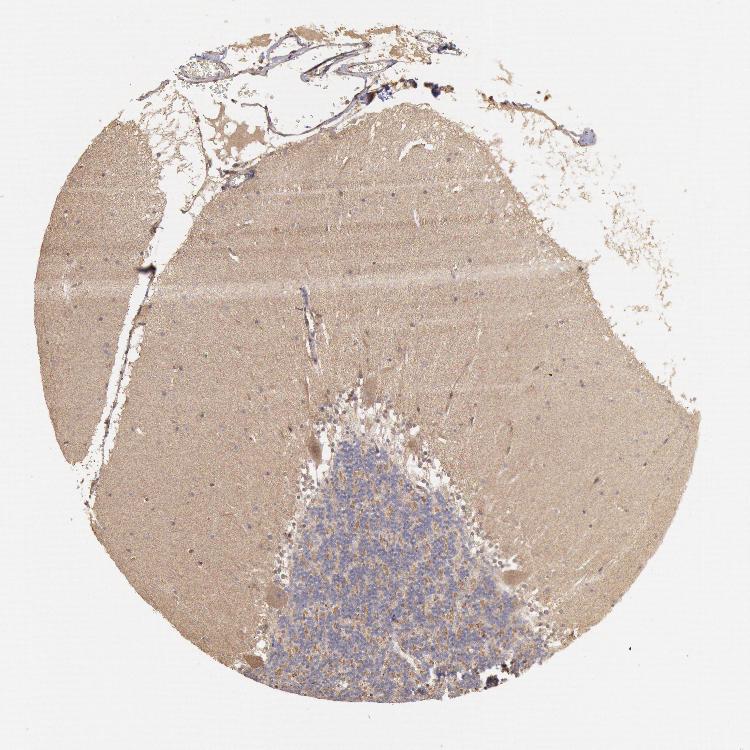

CEREBELLUM - Antibody stainingi

Antibody staining in the annotated cell types in the current human tissue is reported as not detected, low, medium, or high, based on conventional immunohistochemistry profiling in selected tissues. This score is based on the combination of the staining intensity and fraction of stained cells.

Each image is clickable and will lead to virtual microscopy that enables deeper exploration of all samples and also displays staining intensity scores, fraction scores and subcellular localization as well as patient and tissue information for each sample.

Antibody HPA001204

Purkinje cells Low

Cells in granular layer Not detected

Cells in molecular layer Not detected